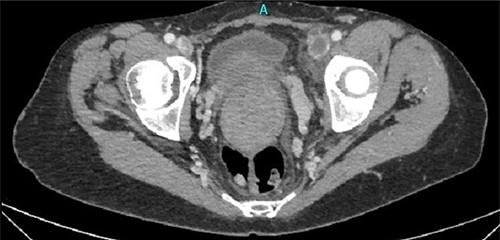

One month later, after vascular consultation, a chest and pelvis computed tomography angiography was performed and a huge mass originating from the uterine wall was revealed (26 cm in diameter) (Fig. 1). The mass compressed the surrounding organs, especially IVC (Fig. 2). Furthermore, thrombosis of left femoral and external and common iliac veins, as well as infrarenal IVC patency (without clarification of IVC thrombosis), was detected. The common, internal and external right iliac veins were patent, and no PE was detected.

A huge mass originating from the uterine wall was revealed after pelvis CTA.